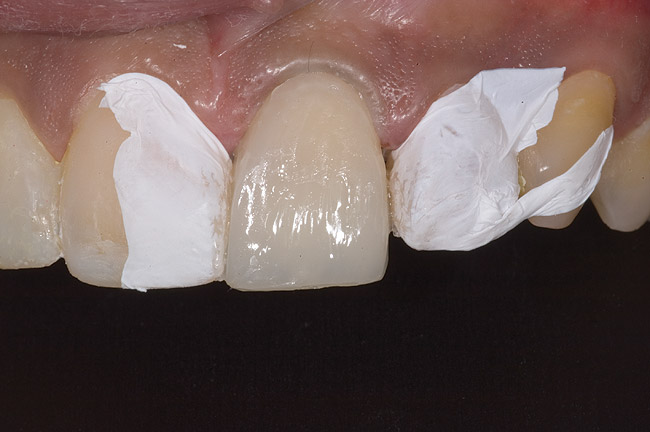

Figure 9: Tooth No. 9 minimally prepared for resin layering on the labial surface.

Figure 9

Figure 10  Tooth No. 9 with no preparation on the palatal surface to restore lost form with bonding resin.

Figure 10